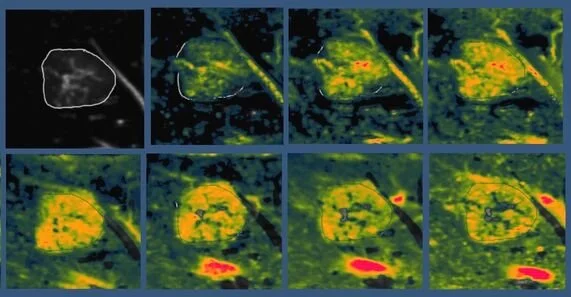

![[Kidney] Normal kidney perfusion, images aligned and averaged.](https://images.squarespace-cdn.com/content/v1/68926c61b505126b7e78f27f/21df7b9a-43f5-462c-b402-2bf5c8868b17/screenshot-2019-03-02-23-16-20.png)

[Kidney] Normal kidney perfusion, images aligned and averaged.